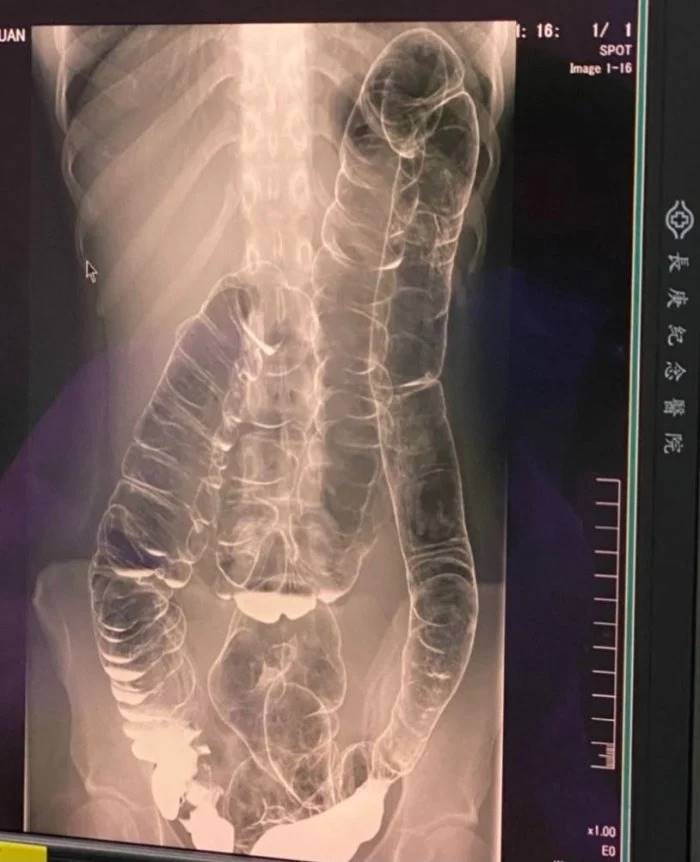

สาวไต้หวันท้องผูกเรื้อรังตั้งแต่เด็ก ไม่ถ่ายหนักนานสุด 17 วัน แชร์ภาพเอกซเรย์ชวนอึ้ง อ้างลำไส้บวมขยายไปถึงหัวใจ ทำโซเชียลตะลึง

แชร์ภาพผลการเอกซเรย์ภายในของเธอ แสดงให้เห็นว่า

ลำไส้ของเธอขดขึ้นไปด้านบนมากกว่าคนทั่วไป

ซึ่งเธออ้างว่ามันขึ้นไปอยู่ในจุดเกือบถึงบริเวณหัวใจ

หลังจากทนทุกข์กับปัญหาดังกล่าวมาหลายปี ในที่สุดเธอก็ตัดสินใจไปพบแพทย์และทำการเอกซเรย์เพื่อดูว่าร่างกายของเธอเป็นอย่างไร และผลเอกซเรย์ปรากฏภาพชวนช็อก นักศึกษาสาวท้องผูกมากจนถึงจุดที่ลำไส้ใหญ่บวมและบีบตัวขึ้นไปด้านบน

ภายหลังจากโพสต์ของเธอถูกเผยแพร่ออกไปในโซเชียลมีเดีย ก็กลายเป็นประเด็นที่ถูกพูดถึงอย่างกว้างขวาง ในขณะที่หลาย ๆ คนตกใจกับภาพเอกซเรย์ มีรายหนึ่งแสดงความคิดเห็นว่า ลำไส้ใหญ่ของเธอขยายจากตำแหน่งของมันไปมาก แต่ยังไม่ได้ไปถึงหัวใจ แค่เธออาจจะมีลำไส้ใหญ่ที่ยาวกว่าคนทั่วไป นอกจากนี้ก็มีคนอื่น ๆ เข้าไปร่วมแชร์ประสบการณ์ที่คล้ายกัน